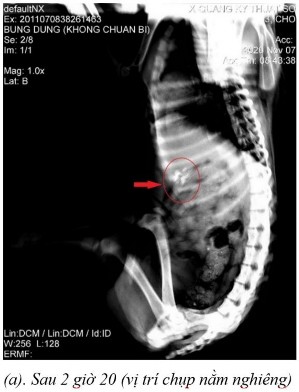

Phụ lục 5.4. Hình ảnh X-quang chó 5 ở thời điểm (a) sau 2 giờ 20 ở vị trí nằm nghiêng, (b) sau 4 giờ ở vị trí nằm ngửa, (c) sau 4 giờ ở vị trí nằm nghiêng, (d) sau 7 giờ ở vị trí nằm ngửa, (e) sau 7 giờ ở vị trí nằm nghiêng, (f) sau 9 giờ ở vị trí nằm ngửa, (g) sau 9 giờ ở vị trí nằm nghiêng, (h) sau 11 giờ 40 ở vị trí nằm ngửa và (i) sau 11 giờ 40 ở vị trí nằm nghiêng